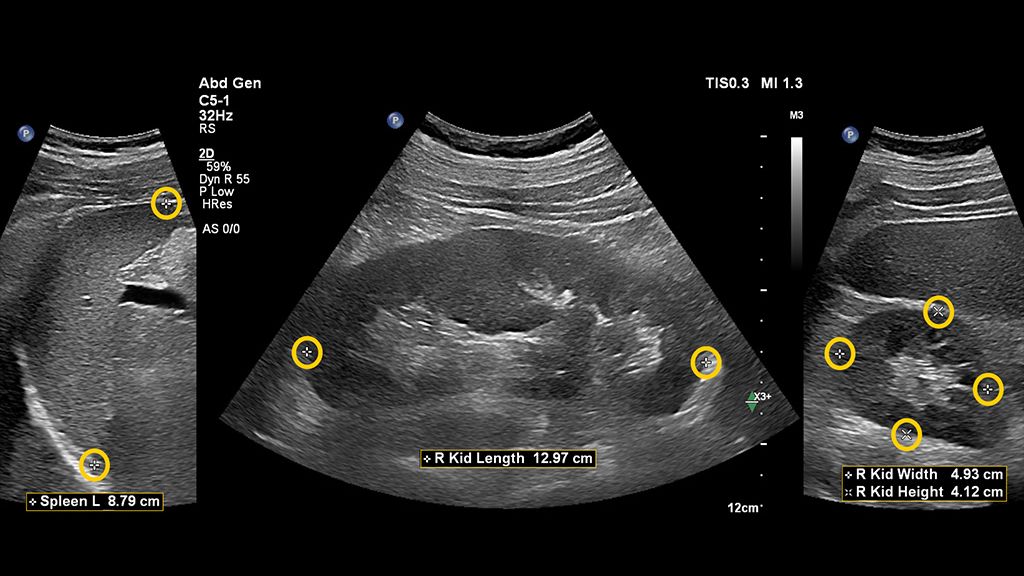

Auto Measure Abdomen

Standard workflow vs. Auto Measure Abdomen workflow

See how much time you can save with Auto Measure Abdomen in this side-by-side workflow comparison video.

The widespread use of this technology in a general population could be helpful in screening for advanced chronic liver disease, especially considering that a complete study can be done in under three minutes using a non-invasive method for chronic liver disease.